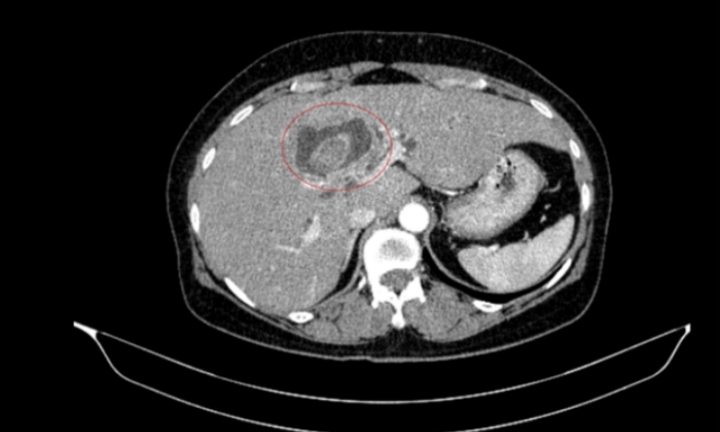

Sau khi cấy máu và cấy mủ vết thương, kết quả cho thấy tác nhân gây bệnh là vi khuẩn tụ cầu vàng. Các bác sĩ điều chỉnh kháng sinh đặc hiệu theo kháng sinh đồ. Song song đó, bà được lọc máu liên tục để hỗ trợ các tạng bị suy.